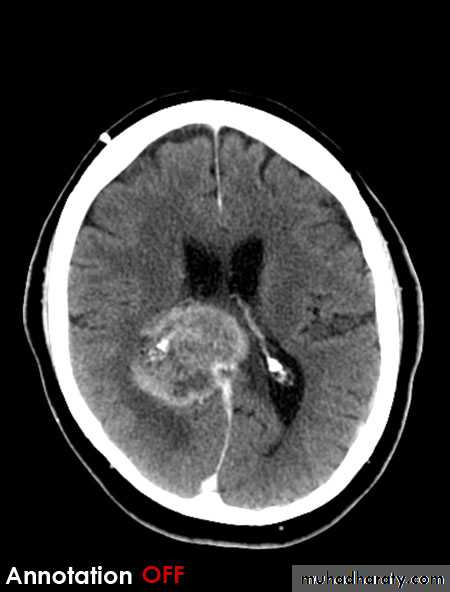

gliobtastoma multiforme G IV highly malignant t. named also as butterfly G. arise from the anterior or posterior aspect of the corpus callosum , extend & spread to both cerebral hemispheric sides

associated hemorrhage , necrosis , & cystic formation

Low grade G. I well or ill defined lesion iso dence to the brain tissues , not associated with oedeme , no Enhancement , no associated Hemorrhage , necrosis .

From G II , III, various previous finding

IV( glioblastoma multiforme ) are highly malignant have all previous mentioned features .